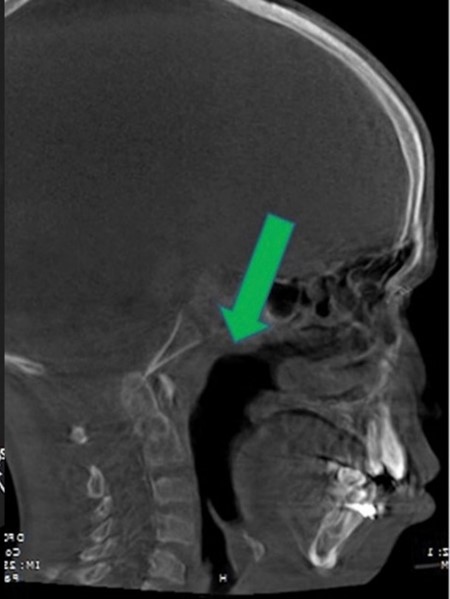

Airway obstruction

2D CT scan showing blocked airway

Radiographical features source 7